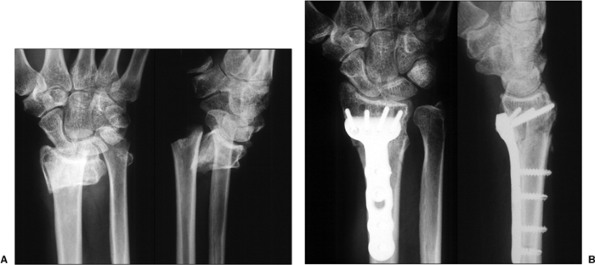

Figure 13.9. An unstable fracture in 56-year-old woman. A. The fracture x-rays. B. Exposure of the pronator quadratus. C.

Following elevation of the pronator quadratus, a needle is placed into the radiocarpal joint marking the distal volar cortical rim. The fracture is reduced. D. The 2.4-mm plate is placed and checked using intraoperative fluoroscopy. E,F. The initial screw is placed in a proximal oval hole that will allow additional stability. G,H. The distal screws with threaded heads permit locking into the plate and angular stable fixation. I,J. Final screw insertion. K. Postoperative x-rays. |